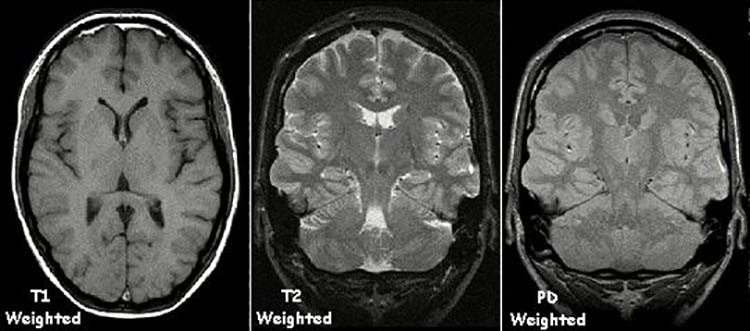

Один из главных инструментов в нейронауках —

магнитно-резонансный томограф. Мы предлагаем подборку из десяти

интересных или просто забавных фактов об этом приборе.1. Индукция магнитного поля Земли 0, 00005 Тесла. Таким образом,